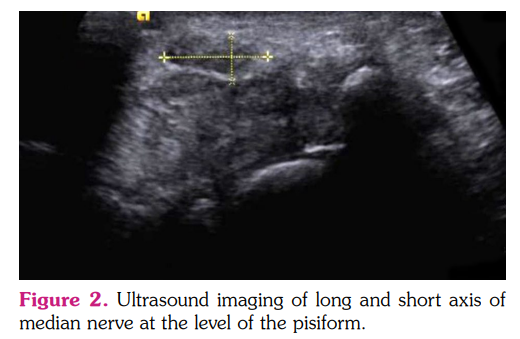

Diagnostic US imaging was performed by a single radiologist specializing in musculoskeletal and neuroultrasound, who was blind to the diagnosis of the patient, the treatment received and other assessment outcomes, before and in the first week following treatment. The scanner used in the study was an Acuson 3000™ (Siemens AG, Erlangen, Germany) with a 9.4 MHz linear array transducer. The patient was seated opposite to the sonographer and the fingers and elbow were flexed and the wrist supinated. Once the transducer was positioned on the volar surface of the wrist, longitudinal and transverse images of the median nerve along its entire course were obtained. The images were obtained from the proximal inlet of the CT at the level of the pisiform and the median nerve CSA was measured. The FR of the median nerve was calculated by dividing the length of its long axis by that of its short axis at the level of the pisiform (Figure 2).[24,25] Palmar bowing was determined by measuring the height from the deep margin of the flexor retinaculum perpendicular to a tangential line drawn between the most volar aspect of the trapezium and hook of hamate at the CT outlet (Figure 3).[26]